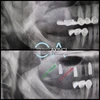

Periimplantitis

Peri-İmplant Mukozitis

Implant tedavisi